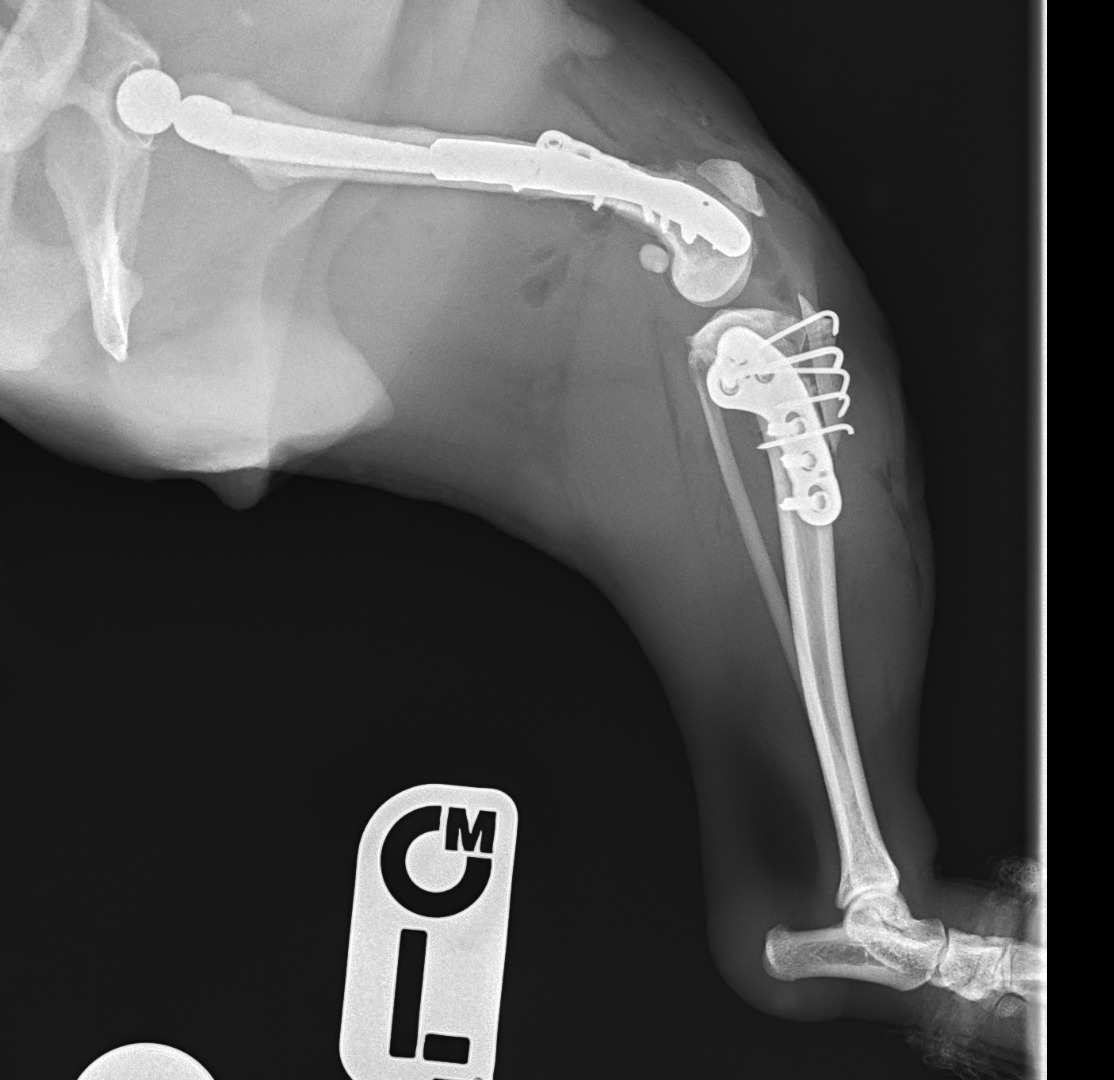

2025年4月24日

手術内容

・左股関節全置換術(根治目的)

人間だとしても大きく難しい手術にドキドキしながら送り出しましたが、「完ぺきにできました」と術後連絡がきて大成功の結果となりました。

2025年5月10日

・右膝蓋骨内方脱臼整復術

– 大腿骨矯正骨切り術

– 内旋制動術

2025年5月24日

・左膝蓋骨内方脱臼整復術

– 脛骨高平部水平化骨切り矯正術(m-CTWO)

2025年7月18日

・右股関節形成不全(根治目的)

・股関節全置換術(右側)

【術中所見】

股関節の円靭帯が断裂していたことが判明。痛みの主な原因はここにあったとみられます。

ぽにょの足にはたくさんの金属がはいっています。

人間でもここまでやるのは大大手術。